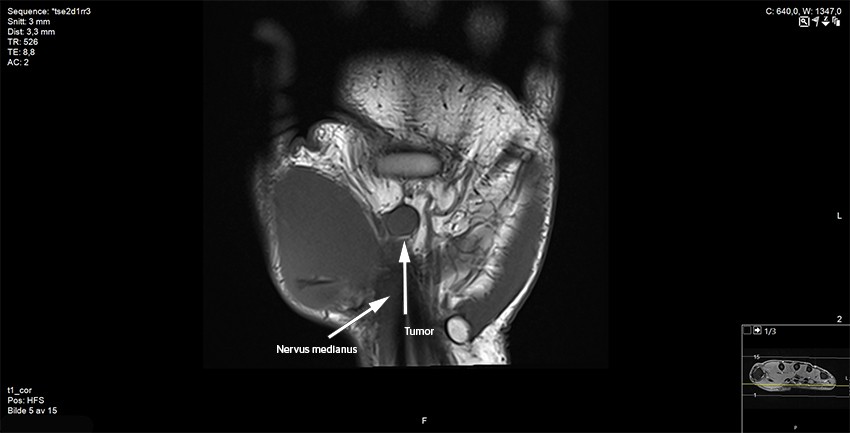

The patient was then referred for an MRI scan at a private clinic and subsequently to the orthopaedic department at the regional hospital. Following the MRI scan, the radiologist reported a contrast-enhancing, well-defined soft tissue tumour adjacent to or on the median nerve at the outlet of the carpal tunnel. It was concluded that the tumour was consistent with a schwannoma, but that another type of tumour could not be ruled out (Figures 2 and 3).